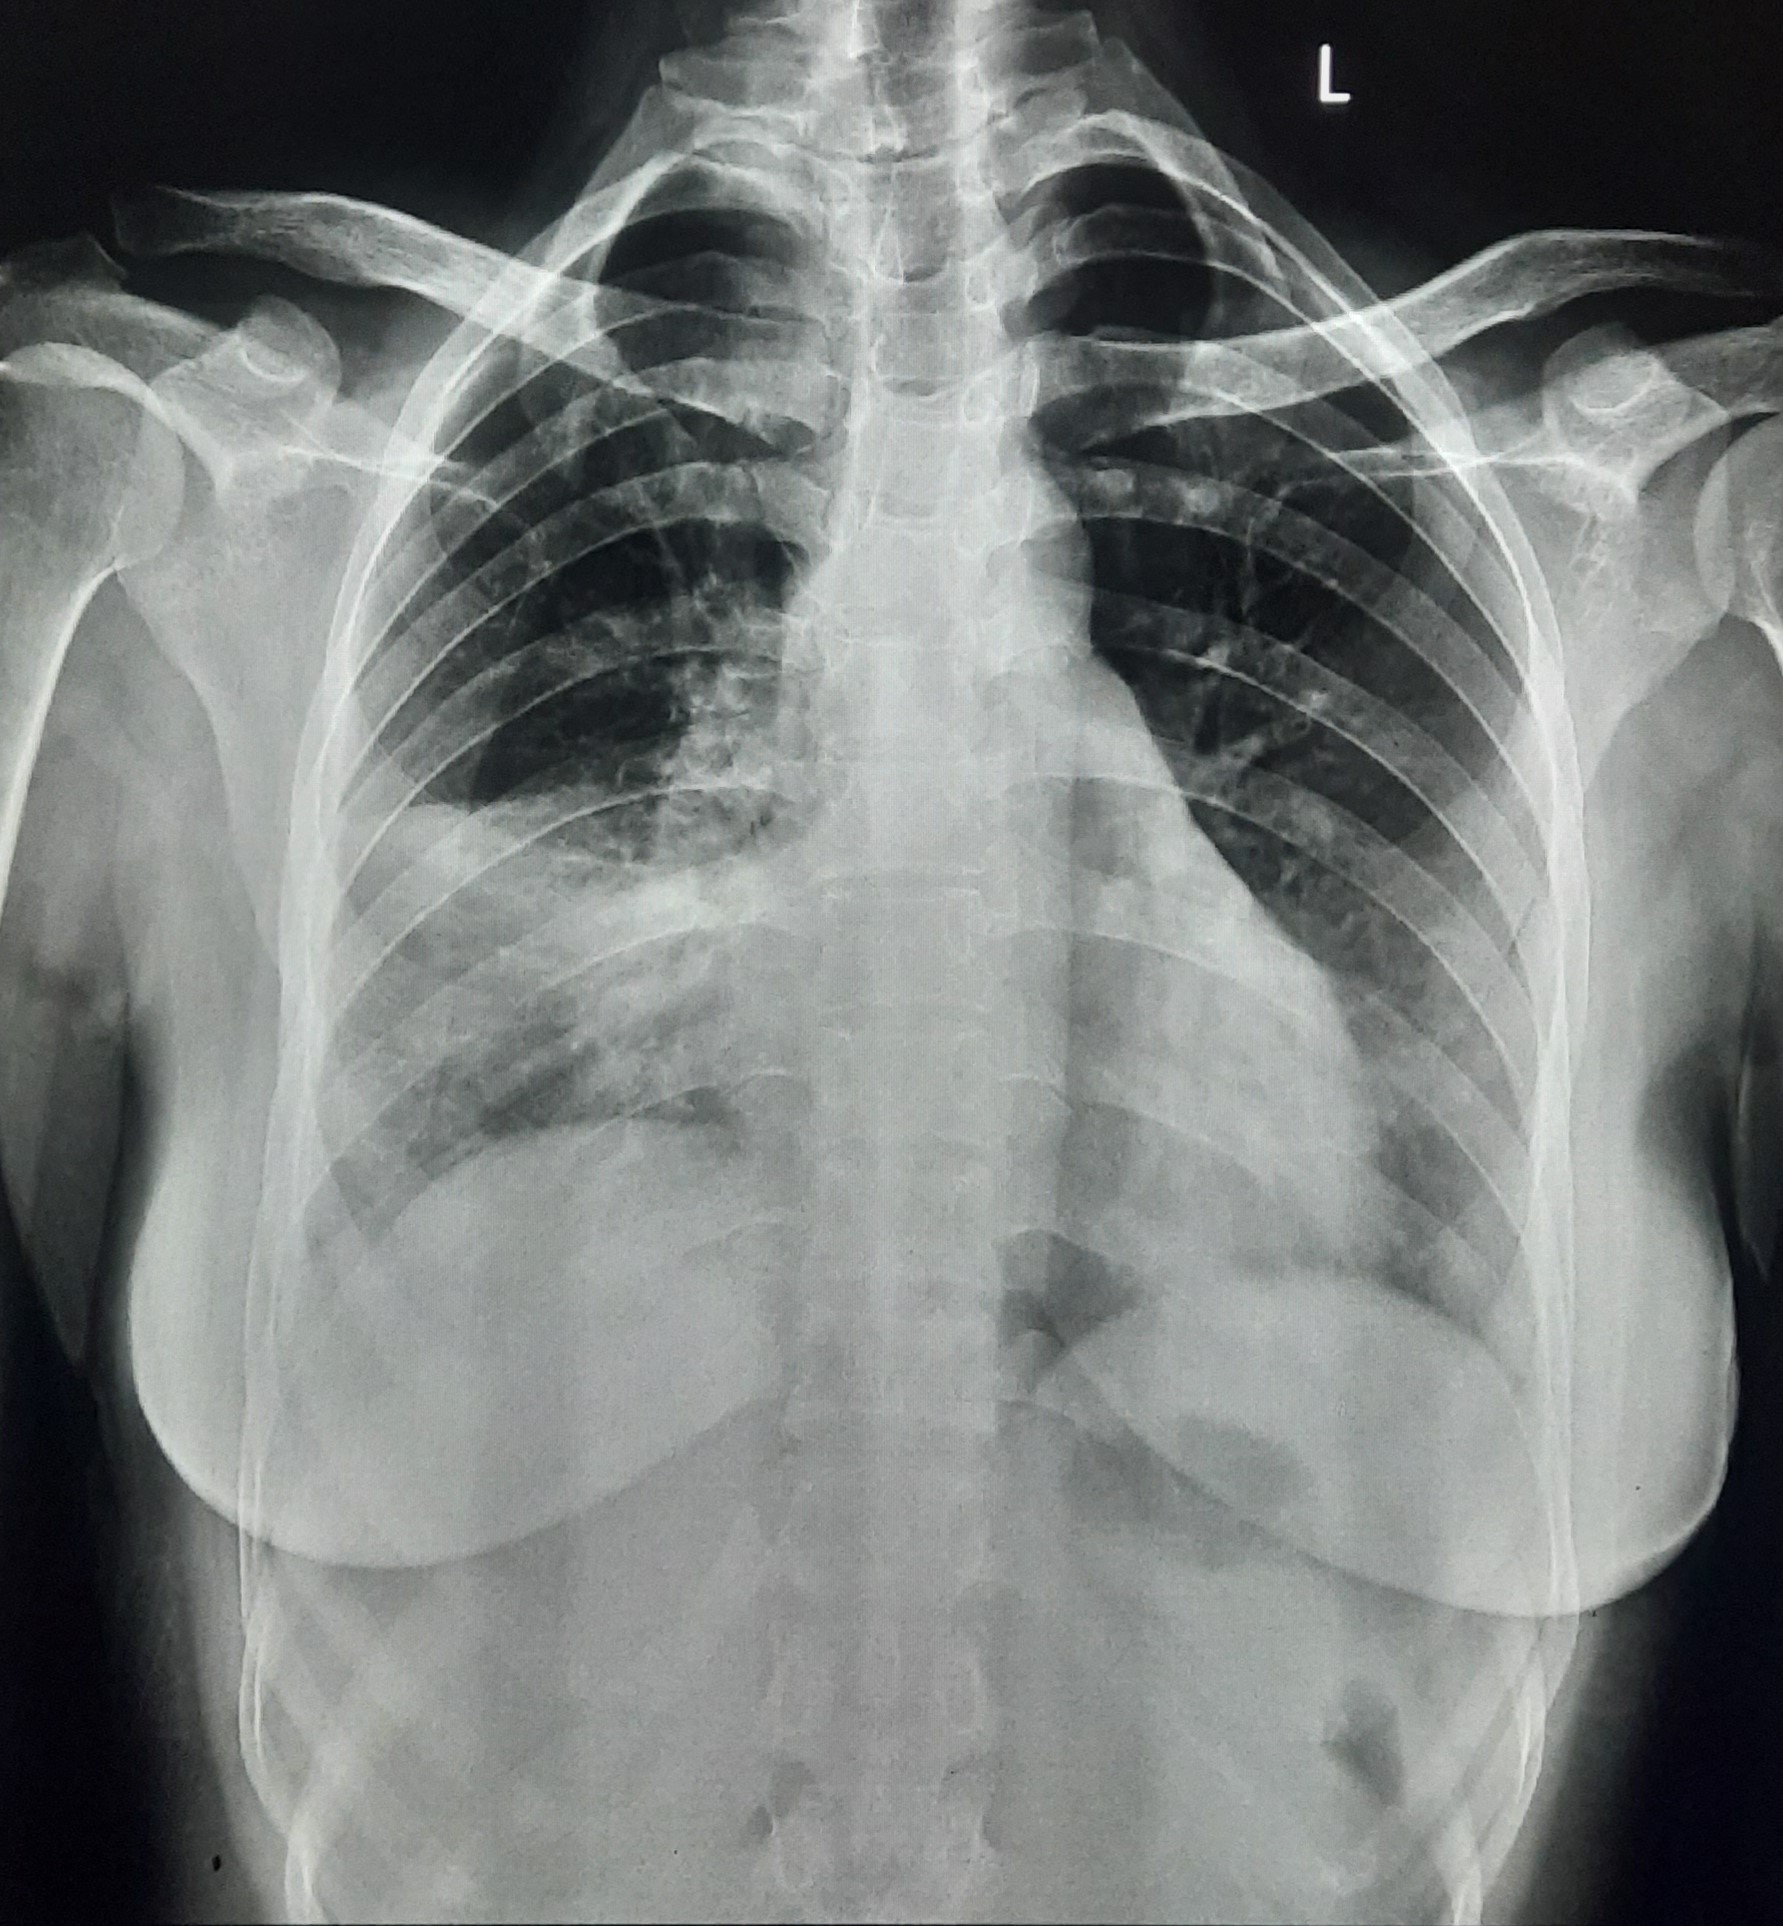

| 151 | IGGMC, Nagpur, Nagpur | P2 | 29-4321 | Chanda Bhowate | Consent taken on Paper | 42 Yrs. |

Provisional Diag : ?

Final Diag : (CxR- Right Sided Synpneumonic Effusion With Pulmonary Infiltration) |

Result awaited (Suspected TB/Non-TB) | Right CP Angle Blunting With Right Lower Zone In-Homogenous Opacity Present With Right Middle Zone/ Lower Zone Infiltration Present | Abnormality visible on x-ray |